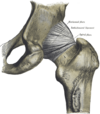

Наружные связки правого тазобедренного сустава: передняя (слева) и задняя (справа)

Внутрикапсулярные связки: слева — левого тазобедренного сустава (удалена часть таза с вертлужной впадиной); справа — правого тазобедренного сустава, вид спереди (удалена капсула сустава).

Суставная капсула к тазовой кости прикрепляется по окружности вертлужной впадины, оставляя вертлужную губу внутри полости сустава. К бедренной кости капсула прикрепляется спереди вдоль межвертельной линии, сзади — немного отступая внутри от межвертельного гребня. Таким образом, шейка бедра располагается в суставной полости.

Связка головки бёдра (лат. ligaméntum cápitis fémoris), находящаяся внутри суставной капсулы, препятствует чрезмерному приведению и наружной ротации бедра. Кроме этой связки тазобедренный сустав укреплён несколькими толстыми, прочными связками, расположенными как в толще капсулы, так и на её поверхности, а именно:

• Подвздошно-бедренная связка(lig.iliofemorale)

• Лобково-бедренная связка(lig.pubofemorale)

• Седалищно-бедренная связка(lig.ischiofemorale)

• Связка головки бедренной кости(lig.capitis femoris)

• Круговая зона